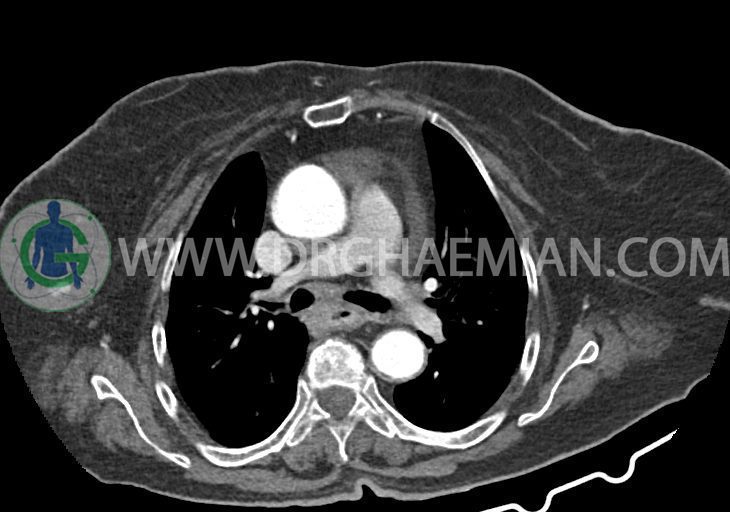

در سی تی اسکن اسپیرال ریه و مدیاستن – شکم و لگن با و بدون کنتراست خوراکی و وریدی (مولتی دیدکتور 16 با مقاطع ظریف و بازسازی های ساژیتال و کرونال):

تراشه و برونش های اصلی نرمال اند. پنومونی، پلورال افیوژن، جابجایی محتویات مدیاستن ، فیبروز ریوی و Collection مشهود نیست.

–کاردیومگالی همراه با pericardial effusion خفیف

–لنف نودهای non significant مدیاستینال با حداکثر SAD=6mm در فضای پره کارینا

–آئورت صعودی دیلاته به قطر 38mm